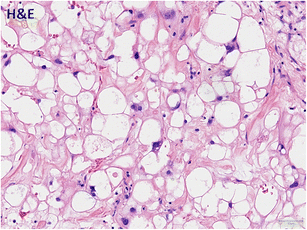

Histopathological imaging. The lesion shows vacuolated tumour cells with a pale cytoplasm and moderate nuclear polymorphism in a chondromyxoid matrix. These findings are a characteristic of chordoma